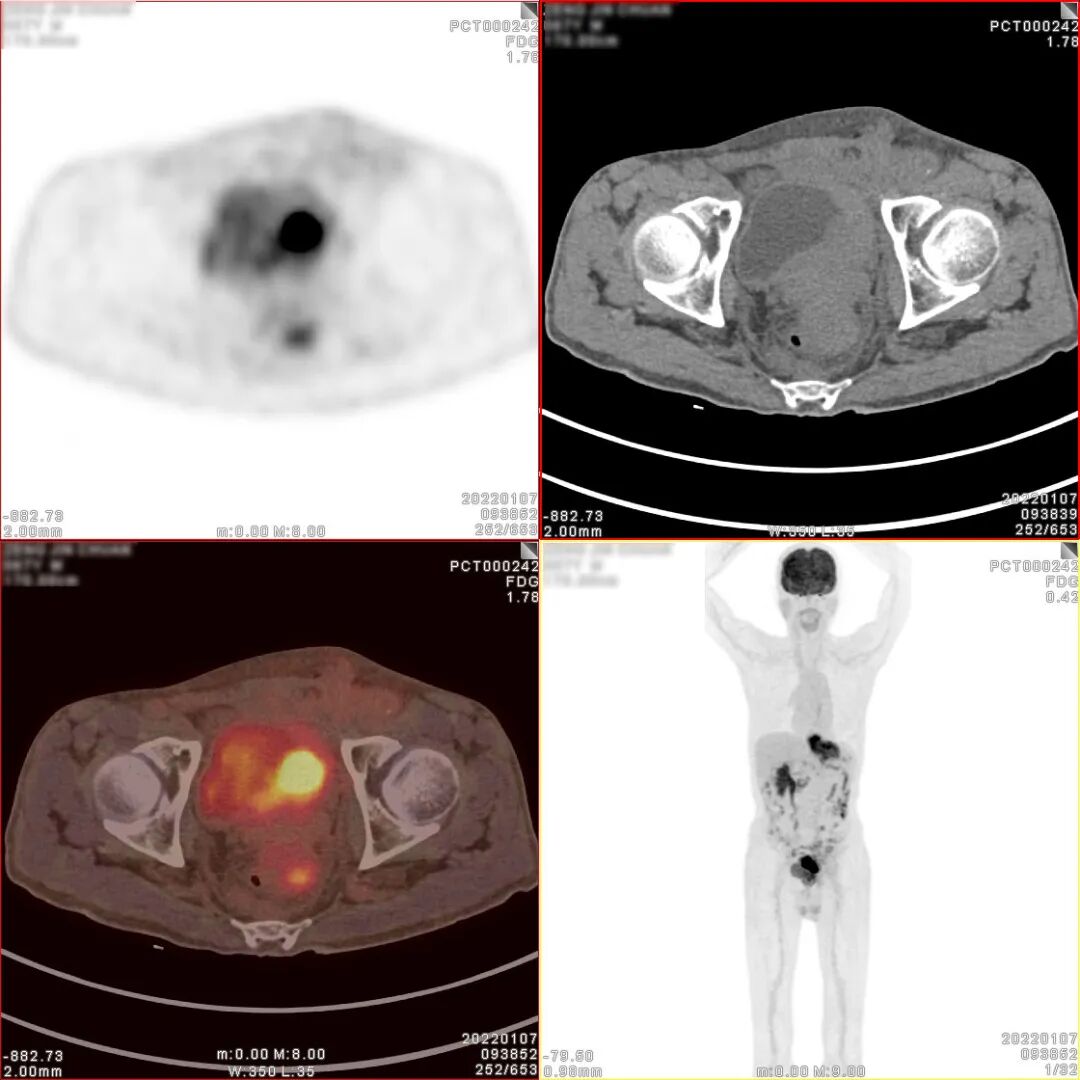

18F-FDG PET/CT检查图像

胃癌术后、化疗后,胃术后缺如,CT 见食管下段与肠道吻合口区软组织明显增 厚,密度较均匀,边缘欠清,PET 于相应部位可见不规则形放射性异常浓聚影,大小 约 71×27×63mm,SUVmax 为 9.5。CT 于左下腹部肠系膜上可见结节状密度增高影, 大小约 14×8mm,密度较均匀,边缘欠清,PET 于相应部位可见结节状放射性异常浓 聚影,SUVmax 为 4.9。CT 见腹盆腔其他部位肠系膜密度稍增高,边缘模糊,PET 于 相应部位未见明显放射性异常浓聚影。CT 见膀胱顶壁、左侧壁、左后壁及膀胱三角 区软组织明显增厚,密度较均匀,边缘欠清,堵塞双侧输尿管下段膀胱入口,并向 下与前列腺分界不清,PET 于增厚的膀胱壁内可见不规则形放射性异常浓聚影,大小约80×34×47mm,SUVmax 为 30.3;CT 见前列腺体积不大,其内可见多个小斑点状 高密度钙化影,PET 于前列腺内可见块状放射性异常浓聚影,大小约 39×36×35mm, SUVmax 为 6.9。CT 于盆腔内右侧髂外血管旁可见稍肿大淋巴结,大小约 10×7mm, PET 于相应部位可见结节状放射性异常浓聚影,SUVmax 为 2.9。

PET/CT诊断:

1、胃癌术后、化疗后,食管下段与肠道吻合口区软组织明显增厚,代谢增高, 考虑肿瘤复发病灶;

2、膀胱顶壁、左侧壁、左后壁及膀胱三角区不规则形代谢增高影及前列腺内块 状代谢增高影,考虑膀胱癌并侵犯前列腺;

3、左下腹部肠系膜上结节状密度增高影,代谢增高,考虑转移灶;腹盆腔其他 部位肠系膜密度稍增高,未见代谢增高,请结合临床追踪复查以排外低代谢腹膜 转移灶的可能;

4、盆腔内右侧髂外血管旁稍肿大淋巴结,代谢稍增高,不排外淋巴结转移灶的可能。